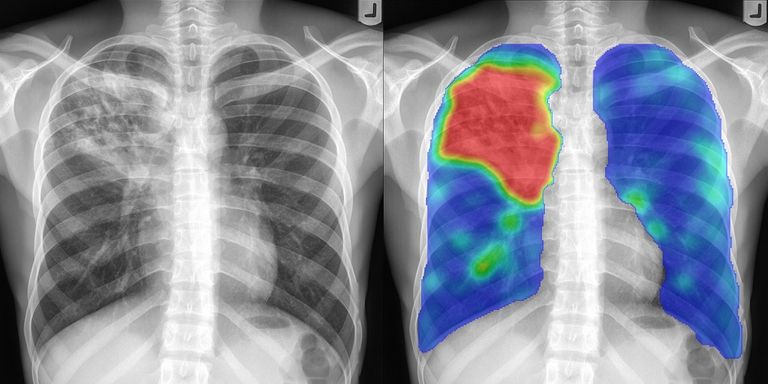

We're excited to help you learn how to analyze X-ray images to spot hidden or ingested items like drugs, weapons, and electronic devices. By the end of this course, you'll have the knowledge and practical skills you need to effectively use X-ray equipment and interpret the images you capture.

X-RAY IMAGE ANALYSIS4Lessons · 2 hr 15 min

Principles of X-ray Image Analysis

Image Analysis

Examples with Real Prohibited Objects